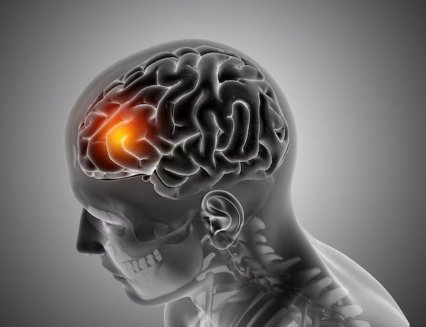

Человек может перенести инсульт, не заметив этого. Инсульт возникает, когда прекращается кровоснабжение части мозга – например, из-а тромба или разрыва кровеносного сосуда. Обычно признаками этого состояния становятся лицевая асимметрия, паралич одной стороны тела, потеря нормальной способности говорить. В то же время существуют и менее...